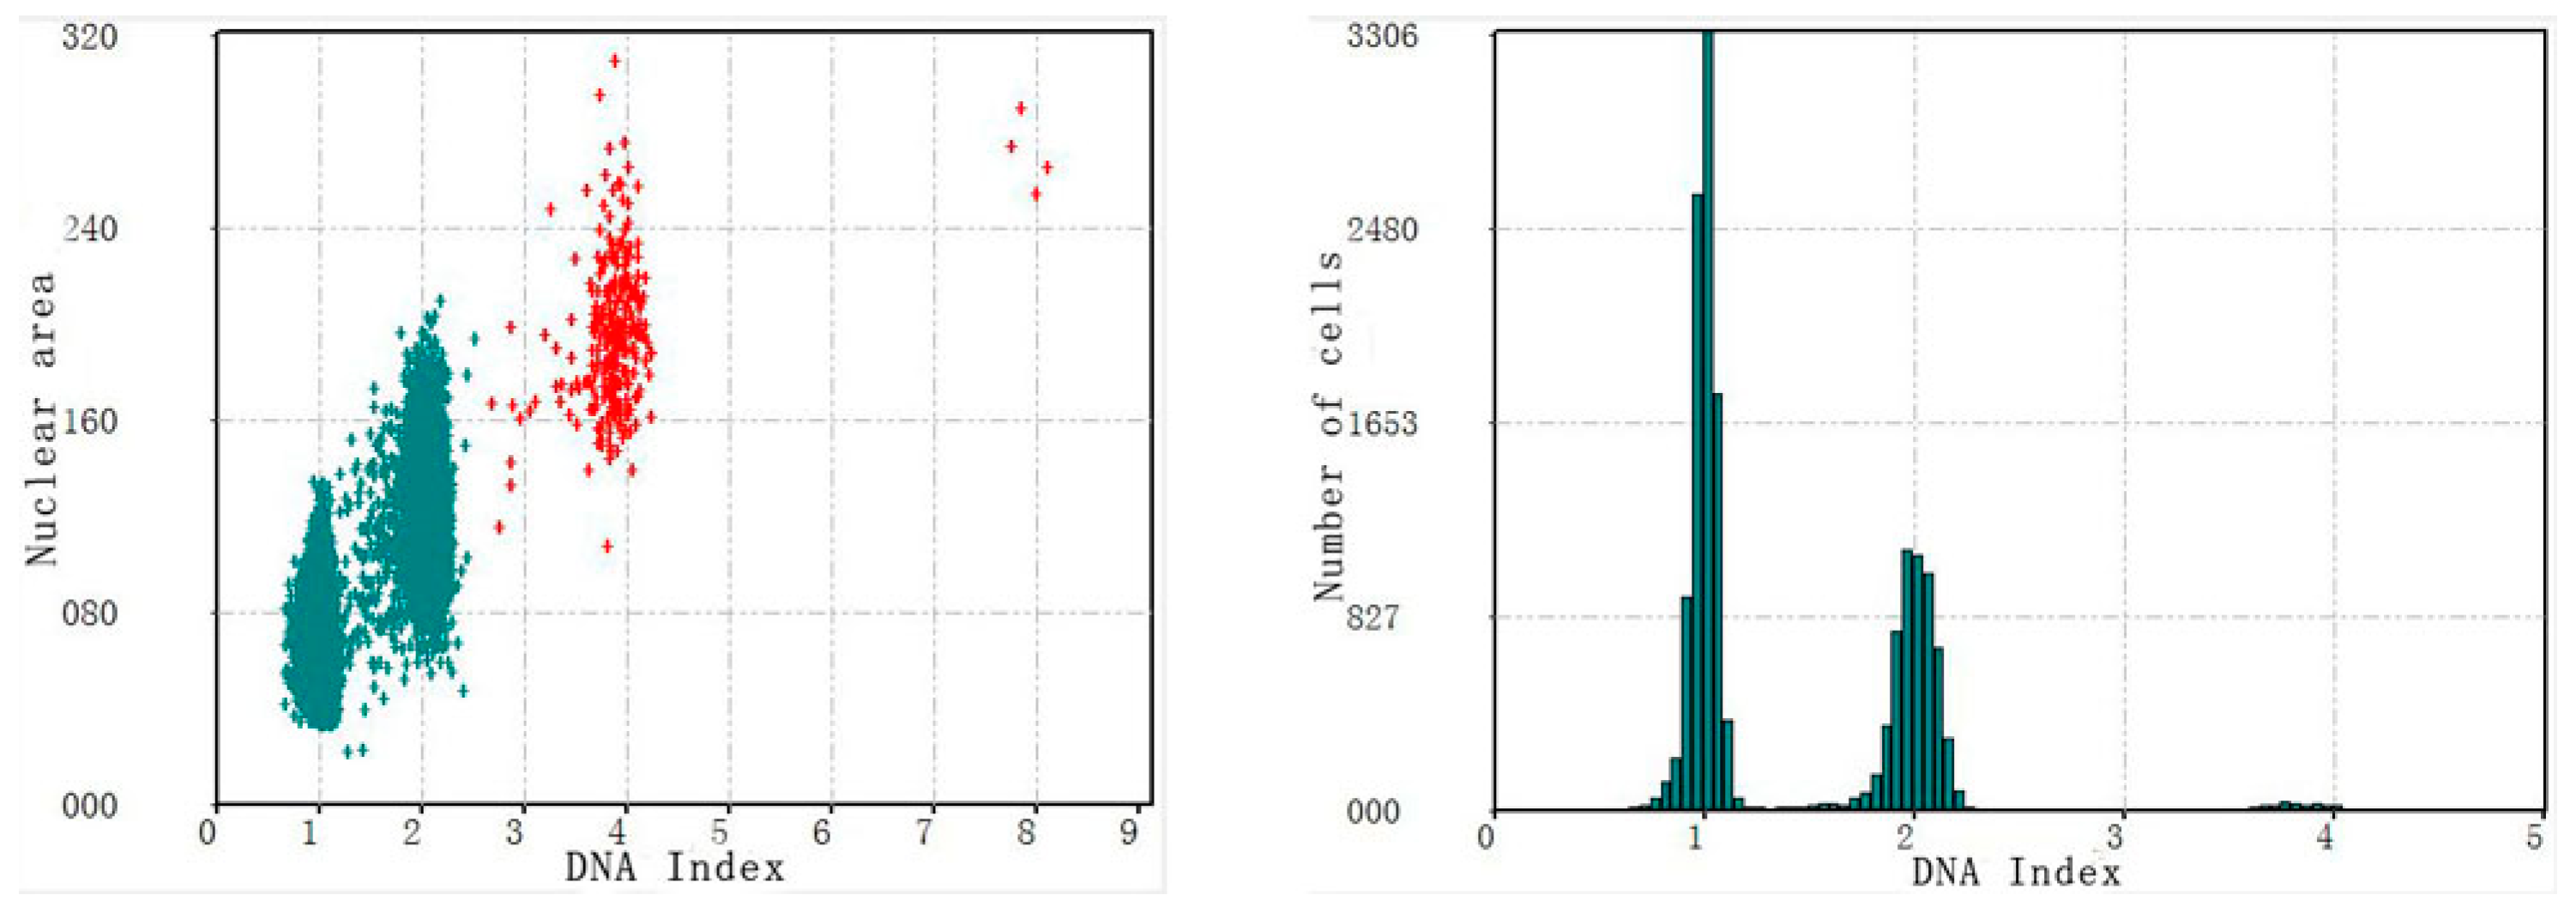

3.2. Verification Test of DNA Quantitative Analysis